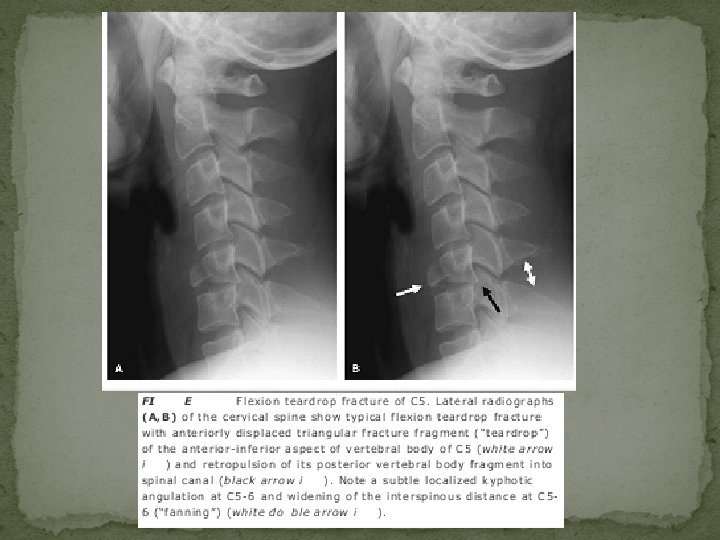

Flexion Teardrop Fracture � represents the most severe injury of the cervical spine � highly unstable injury � typically involving the lower cervical spine (especially C 5) � there is also complete disruption of all soft tissues at the level of injury, including the posterior longitudinal ligament, intervertebral disc, and anterior longitudinal ligament � typical large triangular fracture fragment of the anteroinferior margin of the upper vertebral body (teardrop fragment) Ø The flexion teardrop fracture can be distinguished from the similarly named hyperextension teardrop fracture by the larger size of the triangular fragment and by distraction of the posterior elements (indicating the flexion mechanism).